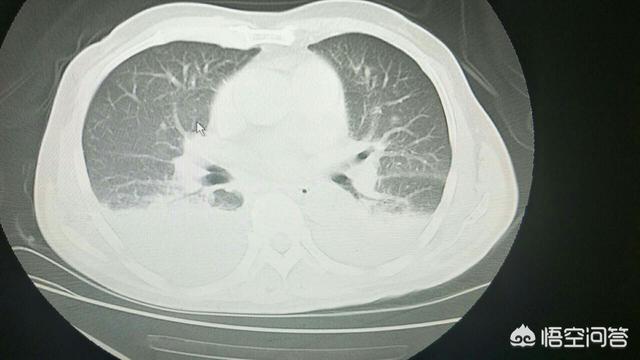

5.呼吸器系 慢性肺炎が多い。

1.肝臓の健康への影響肝臓はアルコール代謝の主要な臓器であるため、長期飲酒の友人、肝臓はあなたのために毎日忙しいです "アルコールを解決する "と、アセトアルデヒドの中間生成物の代謝過程におけるアルコールは有毒物質であるため、長期飲酒の友人、最も直接的な影響は、肝臓の健康であり、軽度のアルコール性脂肪性肝疾患が表示されることがあり、または肝硬変に発展し続ける可能性があり、肝機能が深刻に損なわれている。の問題、またはそれは肝硬変、肝機能の深刻な障害の問題に発展し、開発し続けることができる。

ワインに含まれるエタノールは肝細胞で代謝され、代謝によって生成されるアセトアルデヒドは肝細胞そのものに強い刺激を与え、肝臓は体内最大の脂肪「処理工場」であり、アセトアルデヒドの刺激によって脂肪合成が増加し、肝臓に多量の余分な脂肪が蓄積してアルコール性脂肪肝の発生につながり、時間が経つにつれて肝細胞はこうなる可能性がある。長期的には、肝細胞は線維化し、肝硬変となり、深刻な結果を招く。